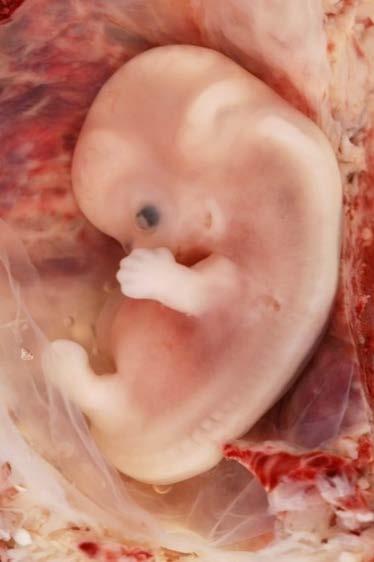

After about 16 days the brain, spinal cord and heart have started to form. By the end of the eighth week the embryo can be recognised as human, and limb buds can be clearly seen. All organs have are present, but they are not functional. Miscarriages are most common during the first trimester as the developing embryo is mostly easily affected by drugs, such as alcohol and nicotine, and pathogens such as rubella and other viruses.Some of the cells that make up the hollow ball of cells (blastocyst) develop into the placenta. The embryo is called a foetus from 8 weeks onwards.

The embryonic period is characterised by the development of all of the body systems. The embryonic period lasts from Week 3 to Week 10 of pregnancy (8 weeks).